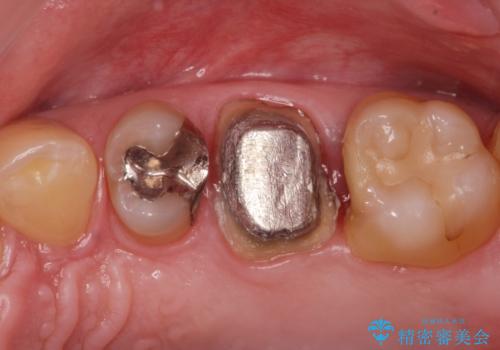

- 銀歯を白くしたいとの事で来院。まずは気になるところから治療していくという事になりました。

銀の被せ物を外し虫歯がないのを確認して、形を整えて白い被せ物の治療を行いました。

(再根管治療の提案をしたがご希望されませんでした。)